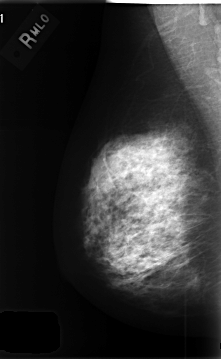

C_0412_1.LEFT_MLO

LEFT_MLO LINES 4472 PIXELS_PER_LINE 2976 BITS_PER_PIXEL 12 RESOLUTION 50 OVERLAY